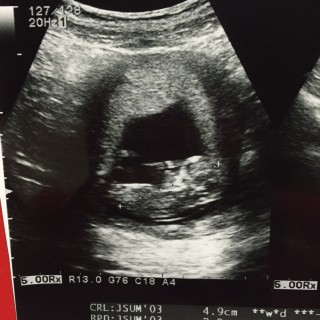

4,9㎝。順調です!右が頭です☆

最新の超音波器具で みてもらいました! 早くも性別発覚!! 素人の私でもすぐにわかりました! 9割男の子ということで ほぼ確定!! 大きさは5.5cm すごいくっきり映っていて 人間の動きをしていて 感動しっぱなし!!

5.34cmでした。足を組みながら指しゃぶりしている様でした(*^_^*)予定日はなんと私の誕生日!